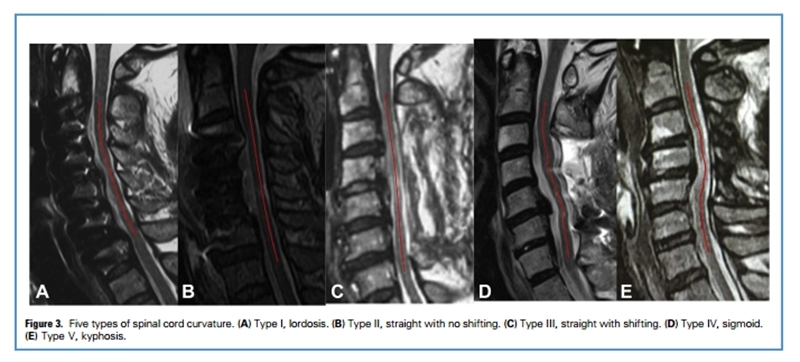

传统后路手术减压的核心原理是扩大后方椎管的空间,使脊髓向后方漂移,实现间接减压。但过度的向后漂移可能造成神经根牵拉损伤,导致术后C5神经麻痹。

史建刚教授在2013年提出采用选择性椎板切除的办法对脊髓进行适当减压,同时限制脊髓的后移,成功降低了后路手术C5神经麻痹的发生率。而如今的ACAF技术更好的遵循了脊髓原位减压的原理。

杨海松副教授通过回顾ACAF治疗的49例伴颈椎后凸的颈椎管狭窄症患者发现,ACAF技术可显著恢复颈椎的生理曲度,更为重要的是,ACAF术后脊髓的矢状面形态从术前的后凸恢复到了前凸的自然形态,实现了脊髓的原位减压。

ACAF术后脊髓曲度恢复到了正常的前凸,这被认为是ACAF技术实现良好神经功能恢复和避免C5神经麻痹的重要原因。